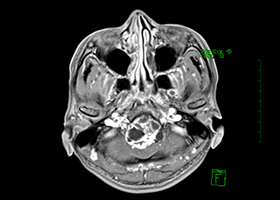

症例3)31歳男性、延髄前面巨大舌下神経鞘腫

[画像所見]

-

嚥下困難、四肢麻痺で発症しました。 -

術前 -

術後 -

術後、患者さんは元気に自宅退院されました。